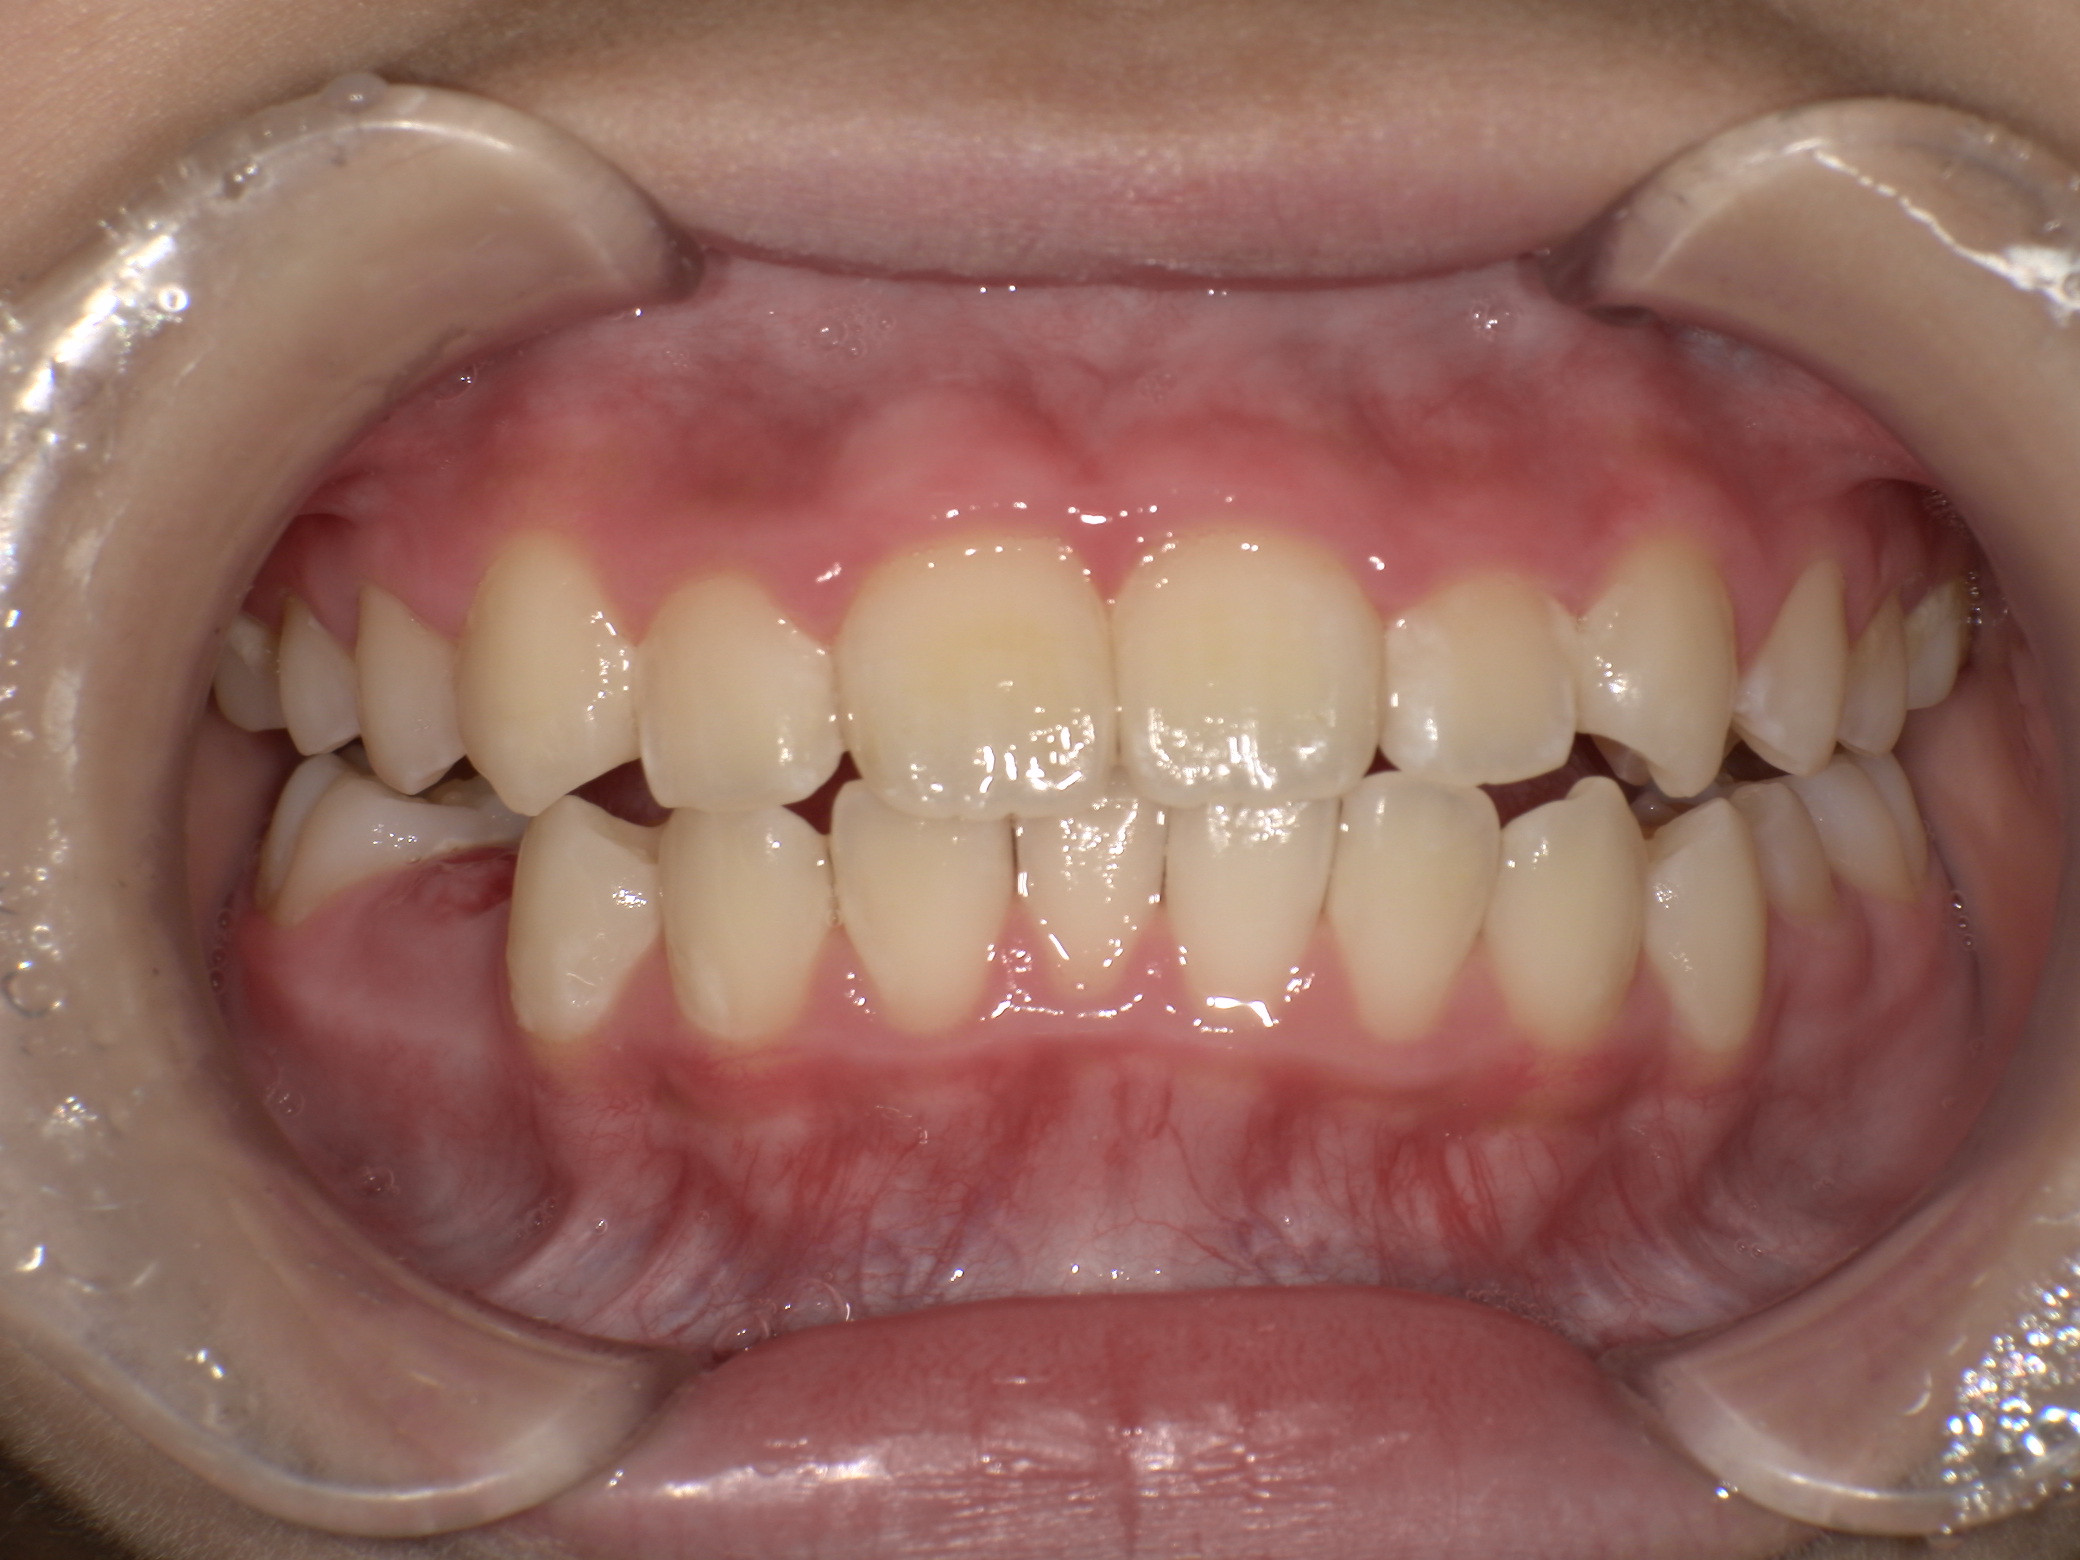

| 年齢・性別 | 男性 |

|---|---|

| 主訴 | 歯並びが気になる |

| 治療期間・回数 | 1年間 |

| 費用 | 330,000円(税込) |